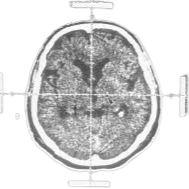

Gambar Otak

Analisis CT Scan: Menggunakan pembelajaran mesin untuk menganalisis gambar CT scan otak untuk deteksi awal penyakit Parkinson